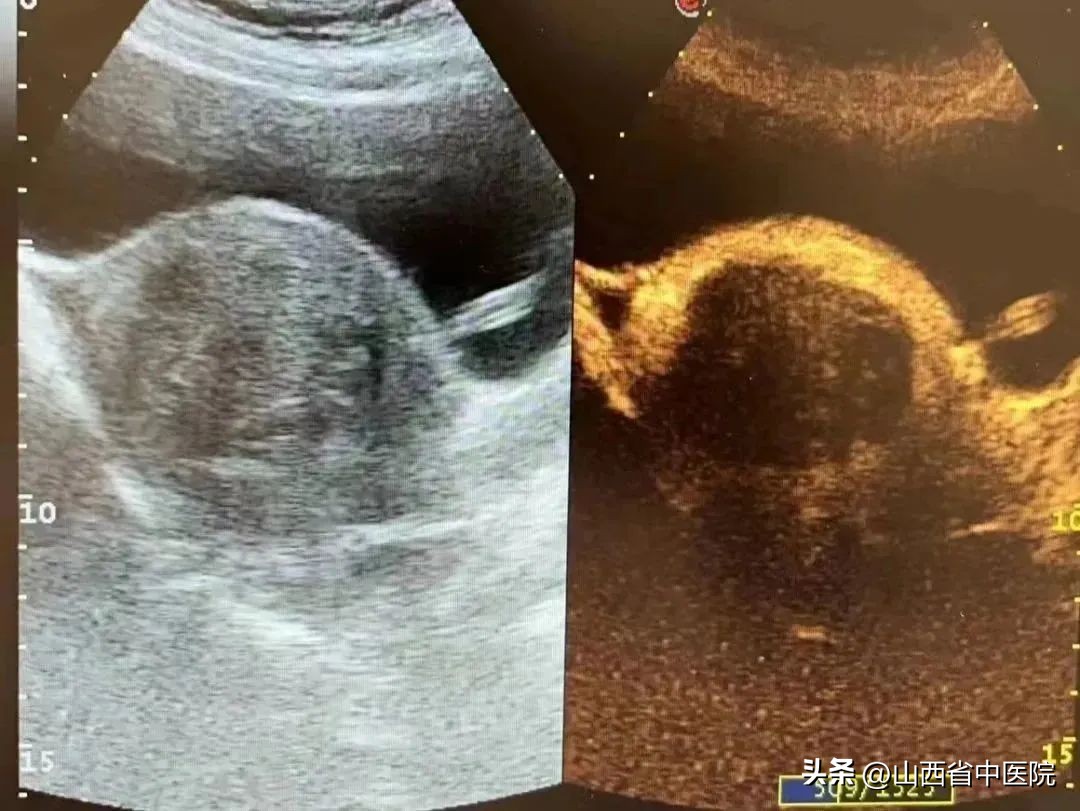

2023年2月8日,市民李女士和张女士就通过山西省中医院妇产科引进的“海扶刀”技术成功治疗了子宫腺肌瘤(5cm)和子宫肌瘤(3cm,5cm)。在“海扶刀”的整个治疗过程中,医生操作仪器,对准影像中出现的肿瘤组织,一个个实现“定向*破爆**”,就杀死了患者体内的子宫肌瘤。

术后疗效:瘤体凝固性坏死,无血流灌注,疗效明显。

海扶手术是高能聚焦超声消融手术,属于无创的局部性治疗方法。利用彩超精准定位病灶,将体外低能量的超声波聚焦于病灶,形成高能量的焦点,使病灶组织凝固性坏死,同时不伤害正常组织,从而达到无创治疗病灶的目的。